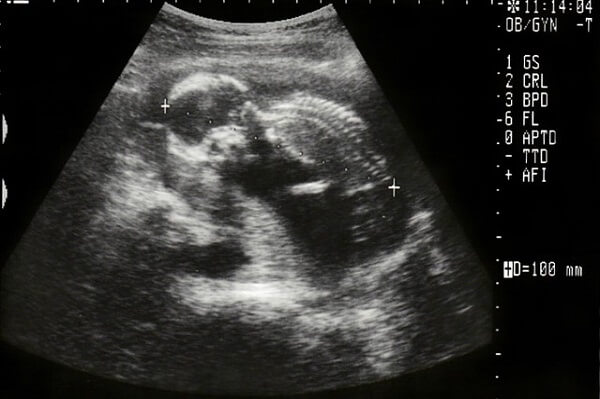

妊娠16週目(妊娠5ヶ月)の赤ちゃんは、身長110~140mm・体重60~120g程まで成長します。エコーでだいぶ人間らしい姿になった赤ちゃんを見ることができます。